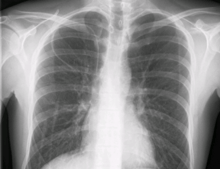

Chest x-ray with catheter in the right subclavian vein

During subclavian vein central line placement, the catheter can be accidentally pushed into the internal jugular vein on the same side instead of the superior vena cava. A chest x-ray is performed after insertion to rule out this possibility.[18] The tip of the catheter can also be misdirected into the contralateral (opposite side) subclavian vein in the neck, rather than into the superior vena cava.

The line is then inserted using the Seldinger technique: a blunt guidewire is passed through the needle, then the needle is removed. A dilating device may be passed over the guidewire to expand the tract. Finally, the central line itself is then passed over the guidewire, which is then removed. All the lumens of the line are aspirated (to ensure that they are all positioned inside the vein) and flushed with either saline or heparin.[1] A chest X-ray may be performed afterwards to confirm that the line is positioned inside the superior vena cava and no pneumothorax was caused inadvertently; electromagnetic tracking can be used to verify tip placement and provide guidance during insertion, obviating the need for the X-ray afterwards.